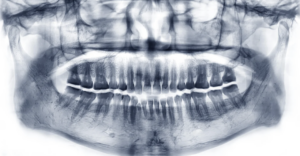

矯正治療を始めるときに必要な検査とは?

こんにちは!くらたやま矯正歯科です。 今回は、「矯正治療を始めるときに必要な検査とは?」についてお話をしていこうと思います。 矯正治療を始める前には、歯並びや噛み合わせの状態を詳しく確認するために、いくつかの検査を行います。これらの検査は、患者様一人ひとりに合った治療計画を立てるためにとても大切なものです。今回は、矯正…続きを読む